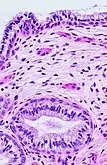

The endocervical mucosa is about 3 mm (0.12 in) thick and lined with a single layer of columnar mucous cells. It contains numerous tubular mucous glands, which empty viscous alkaline mucus into the lumen.[4] In contrast, the ectocervix is covered with nonkeratinized stratified squamous epithelium,[4] which resembles the squamous epithelium lining the vagina.[17]: 41 The junction between these two types of epithelia is called the squamocolumnar junction.[17]: 408–11 Underlying both types of epithelium is a tough layer of collagen.[18] The mucosa of the endocervix is not shed during menstruation. The cervix has more fibrous tissue, including collagen and elastin, than the rest of the uterus.[4]

The squamocolumnar junction of the cervix, with abrupt transition: The ectocervix, with its stratified squamous epithelium, is visible on the left. Simple columnar epithelium, typical of the endocervix, is visible on the right. A layer of connective tissue is visible under both types of epithelium.